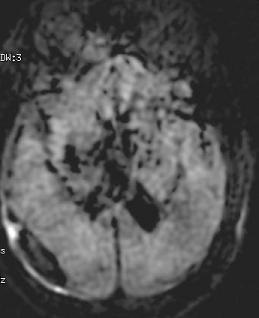

Signal voids

Signal voids can appear in diffusion weighted images produced by DW PROPELLER and are often indicated by black holes, but it may not occur with every scan.

Signal voids may be caused by system calibrations out of spec (e.g., eddy currents).

Contact service to ensure the system is within specification.